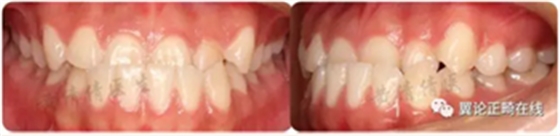

一個(gè)恒牙列早期的骨性3類小女生,沒有顯著家族遺傳史。

磨牙尖牙均為近中關(guān)系,前牙反覆頜較深,下切牙舌傾代償(IMPA=88.8度)。下頜可以功能性后退至切對(duì)切。

從軟組織面型上看,患者面中份發(fā)育尚可,面下1/3發(fā)育過度。下唇外翻明顯。

治療后咬合狀態(tài)、側(cè)貌、以及微笑弧等都得到很大改善。